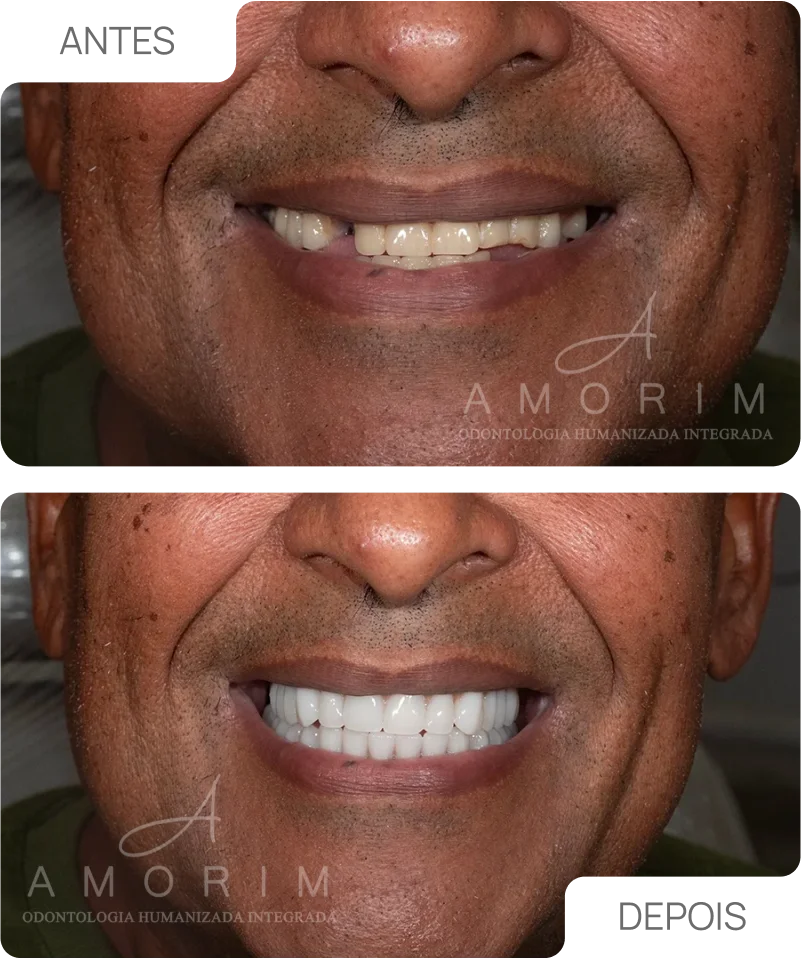

A harmonização orofacial é um conjunto de procedimentos que tem como objetivo equilibrar e realçar a beleza natural do rosto, respeitando as características únicas de...